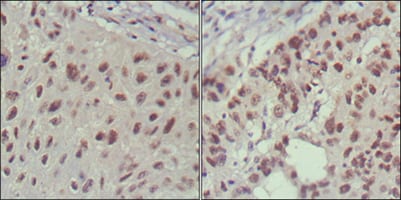

分类: 科研抗体货号: 20357别名: HAP; ASYIP; NSPL2; NSPLII; RTN3-A1应用: IHC反应种属: Human

分类: 科研抗体货号: 20369别名: eN; NT5; CD73应用: IHC反应种属: Human